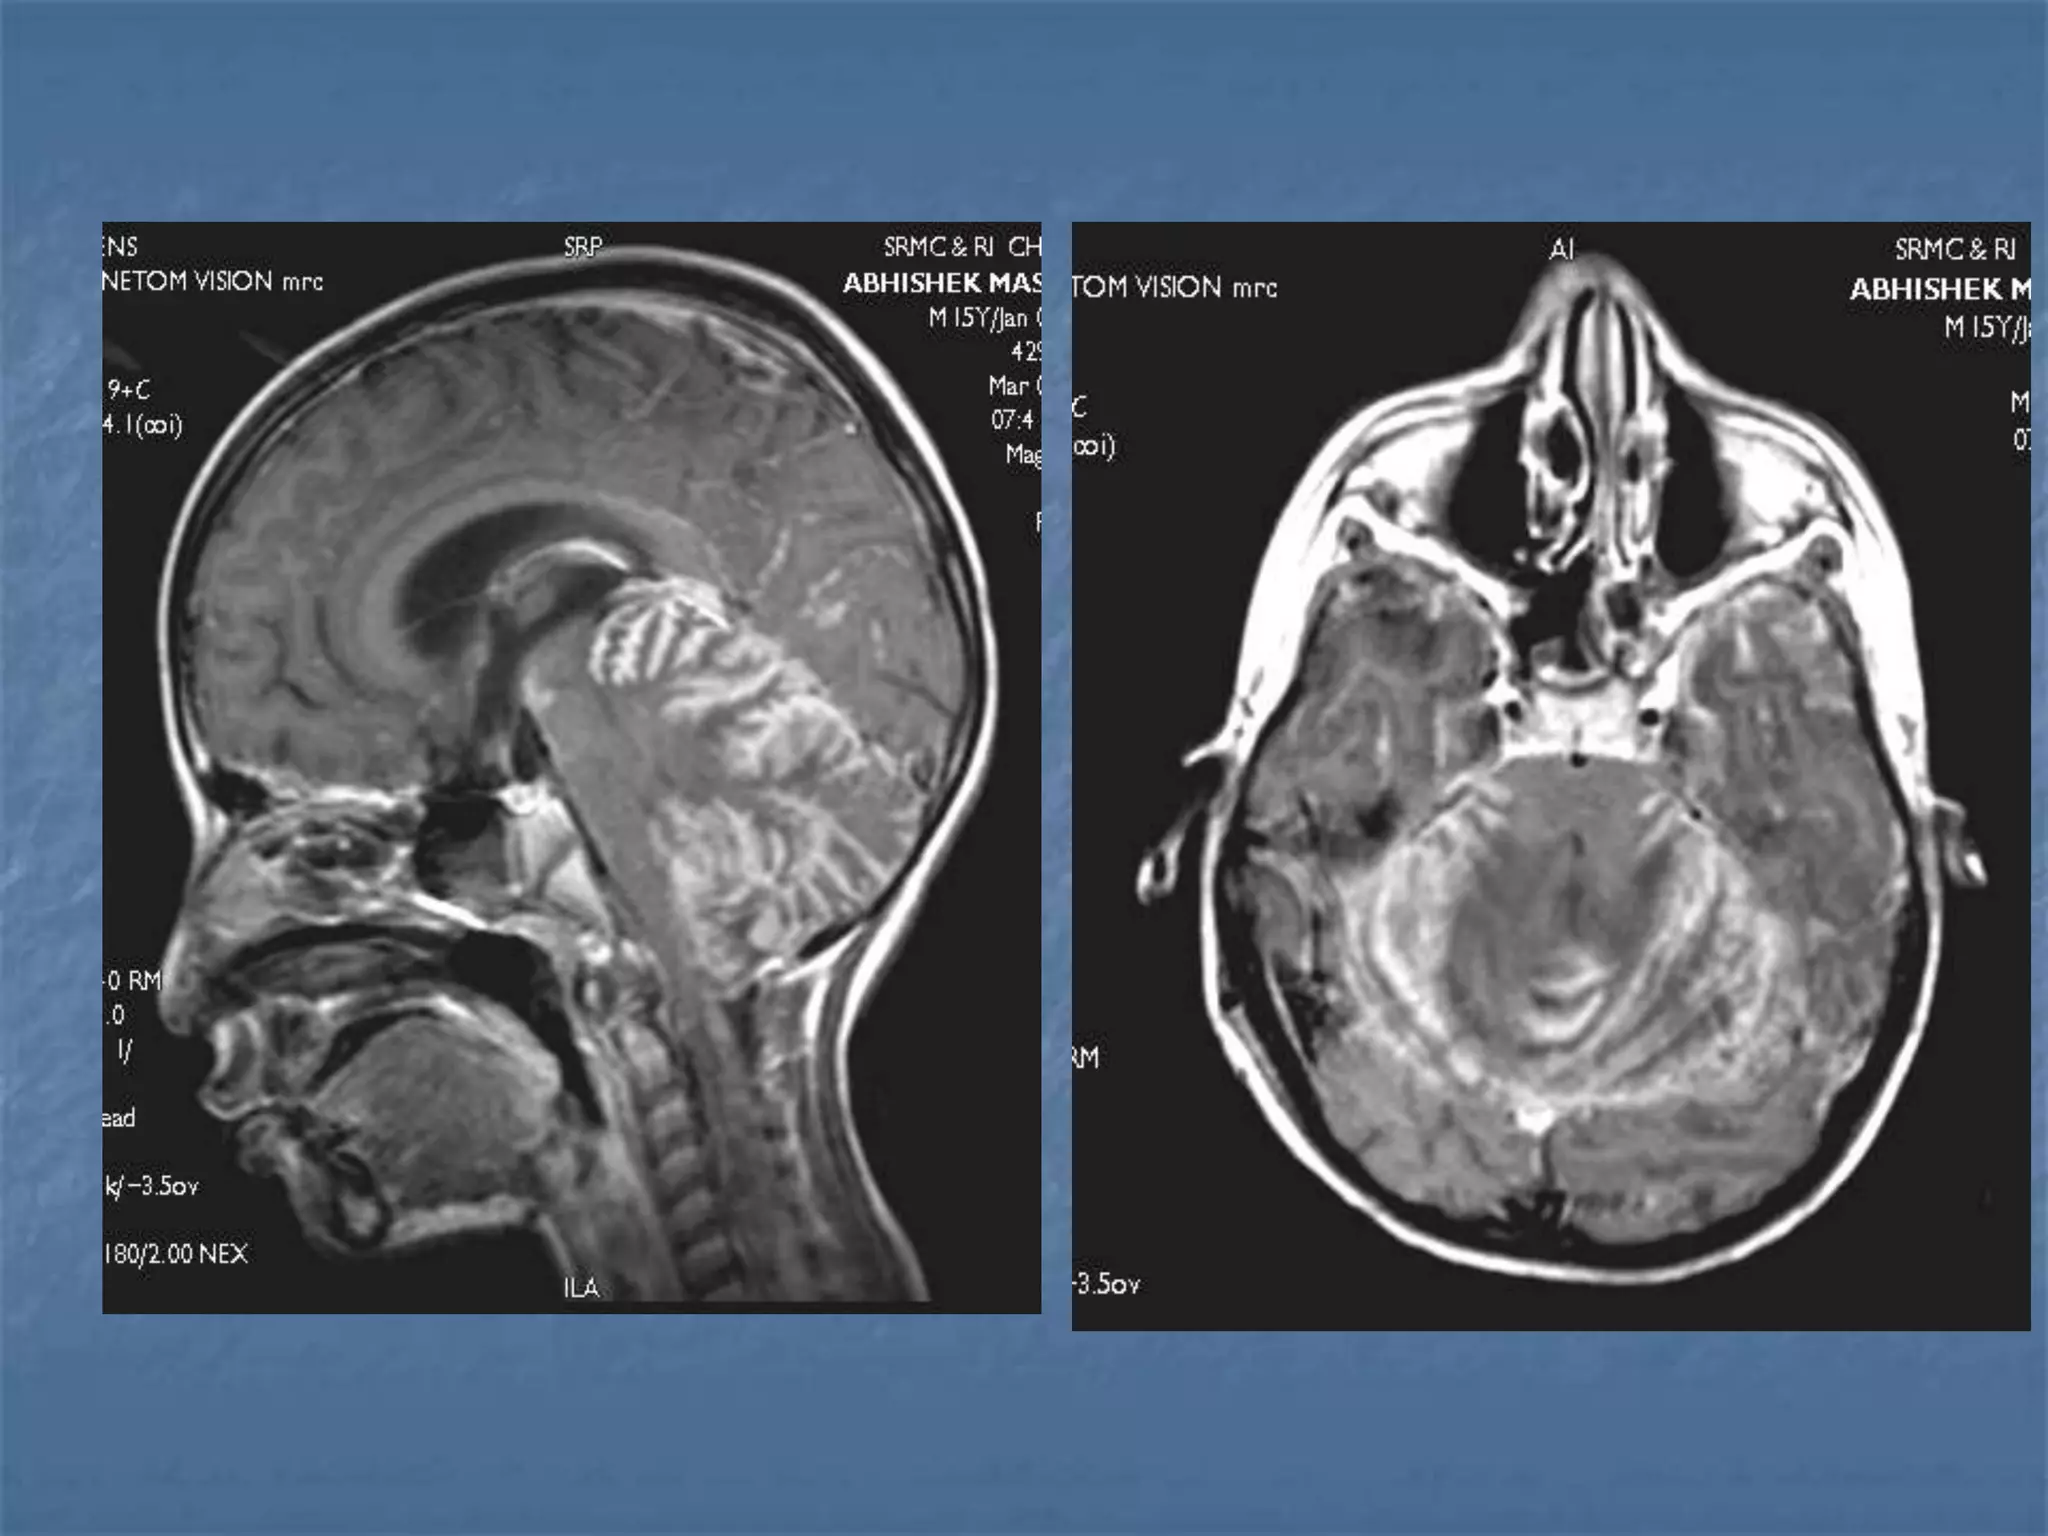

Stroke in Children Constitutes 3% of cerebral infarcts

 Most common cause is congenital heart

disease. Other causes are vasospasm &

vasculitis,

 Echo, CT, MRI & catheter angiogram

should be performed as and when

required.